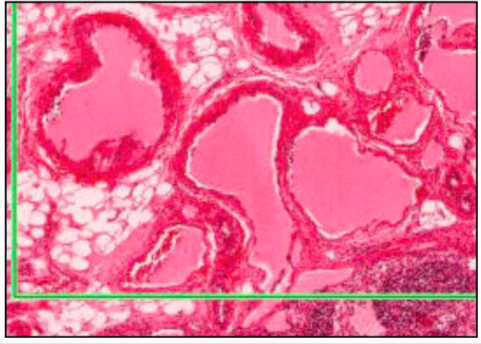

ARTERY - LEFT, VEIN - RIGHT

- 3 layers

- intima (innermost) - endothelial cells on loose connective tissue w/ occasional myo-intimal cells (contractile potential)

- media (middle) - thicker in arteries than in veins - smooth muscle, elastic, collagen

- adventitia (outermost) - dense collagen and elastic

MUSCULAR ARTERY

- well defined medial layer (smooth muscle in concentric rings)

- medial layer interspersed with elastic

- media-intima divide = wavy internal elastic lamina (condensed perforated elastic)

- adventitia-media divie = external elastic lamina only in large muscular

ARTERIOLES

- 3 layers or fewer of muscle @ media

- no internal elastic lamina - therefore amy completely close when muscle contracts

- poor adventitia - mainly collagen and elastin

function: highly responsive to vasoactive stimuli - regulation of TPR

CAPILLARIES

- sometimes have contractile pericytes along bed

- continuous or fenestrated (gut, kidney glomerulus, endocrine glands)

- diameter is size of RBC

this slide - mature adipose

VENULES

- thin walled

- pericytes alongside them

- pericytes become continuous as vessel gets bigger

- in veins no pericytes, replaced by smooth muscle

- irregular outline

VEINS (TOP LEFT x2)

- same layers as arteries, but thinner and poor boundaries

- irregular outline, large lumne (therefore same blood at lower pressure)

- wider lumen than arterioles (but slower flow) therefore same volume/sec